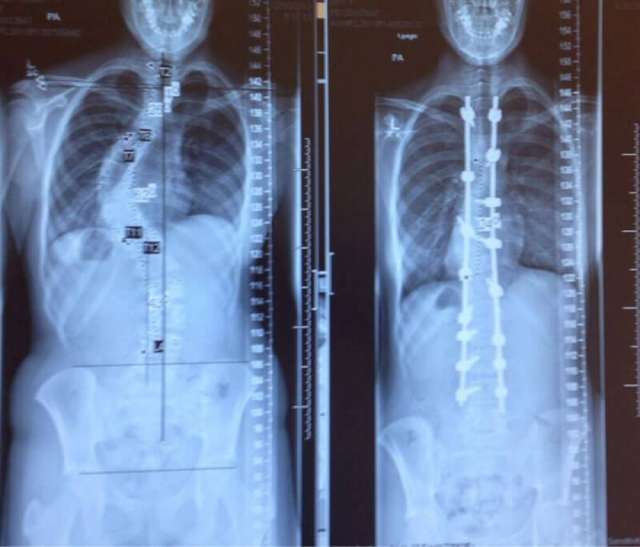

Մարդու ողնաշարը սկոլիոզի և դրա բուժումից հետո